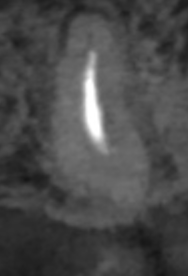

Post-op

臨床にも見事役立つ形成方法のコツであった。